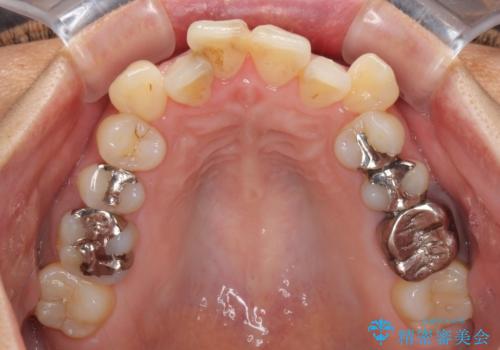

- 八重歯と、それによる口元の膨らみを気にして来院された患者様です。

八重歯・デコボコの解消とともに、前方に張り出した上顎前歯を引っ込めることを目的とし、上下左右の第一小臼歯4歯を抜歯をしてワイヤー矯正により治療することとしました。